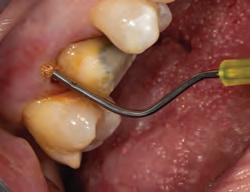

Sable Seek caries indicator contains FD&C dyes, and Seek caries indicator contains D&C dyes in a glycol base. Both are used to stain carious and demineralized dentin.

Seek and Sable Seek caries indicators stain carious and demineralized dentin and can be very useful for difficult-to-see areas, for example; undercuts of preparations, dark dentin, areas along the DE junction, etc. Green Sable Seek caries indicator helps visualization of decay in deep caries cases to help avoid pulp exposures.

PROCEDURE

dentin) with slow-speed round bur or excavator. To control overexcavating near the pulp, remove final portion of caries with hand excavator.